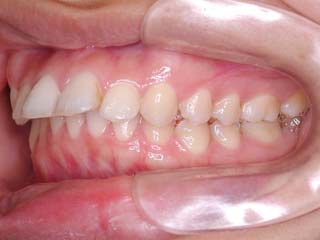

主訴:前歯が出ている

診断名:叢生を伴う上顎前突

かなり強い上顎前突を示します。その他の問題はなさそうですが、小臼歯抜歯だけでは上顎前突に対応しきれそうにありません。上顎大臼歯に最大限の固定が必要と考えられましたので、上顎左右の臼歯部に計2本の歯科矯正用アンカースクリューの植立を検討してみました。